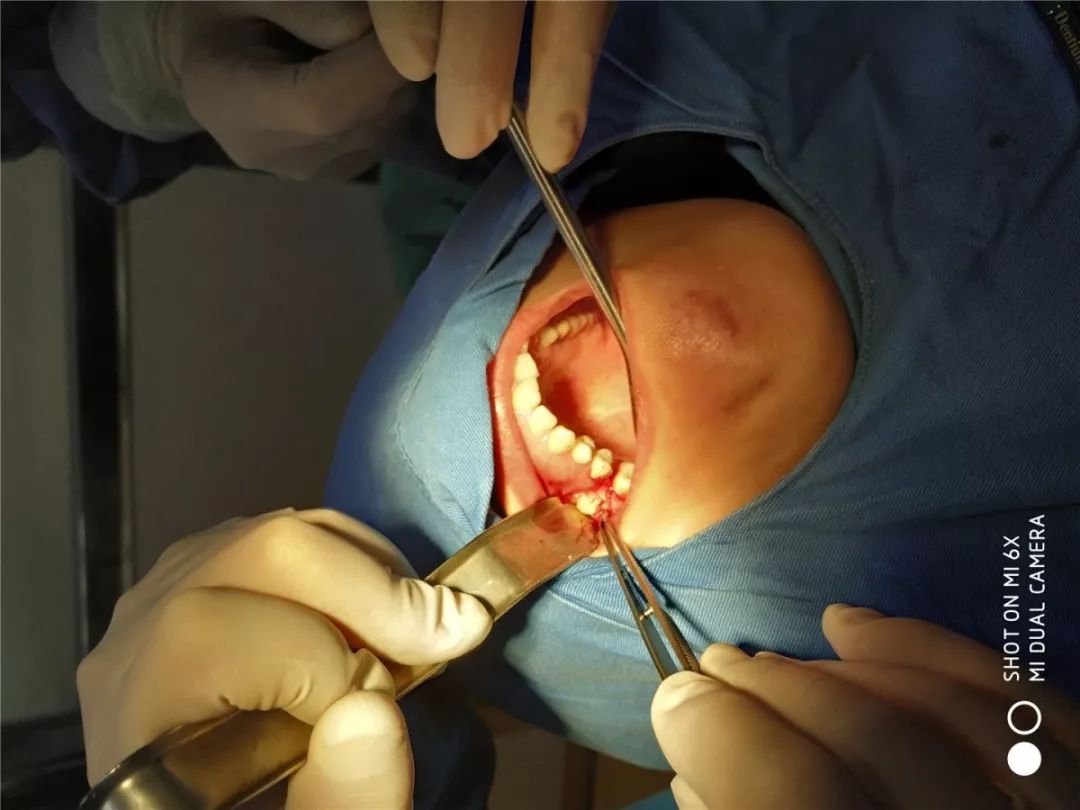

学习班同时举办了Nobel、WEGO口腔种植实操培训和超声骨刀的操作培训。实操期间进行了5台种植手术,包括应用超声骨刀进行的高难度上颌窦外提升并同期植入种植体的手术。16名实操学员通过学习,掌握了种植的外科操作和种植体上部结构及印模技术,具备了开展种植牙技术的能力,所有学员满载而归。